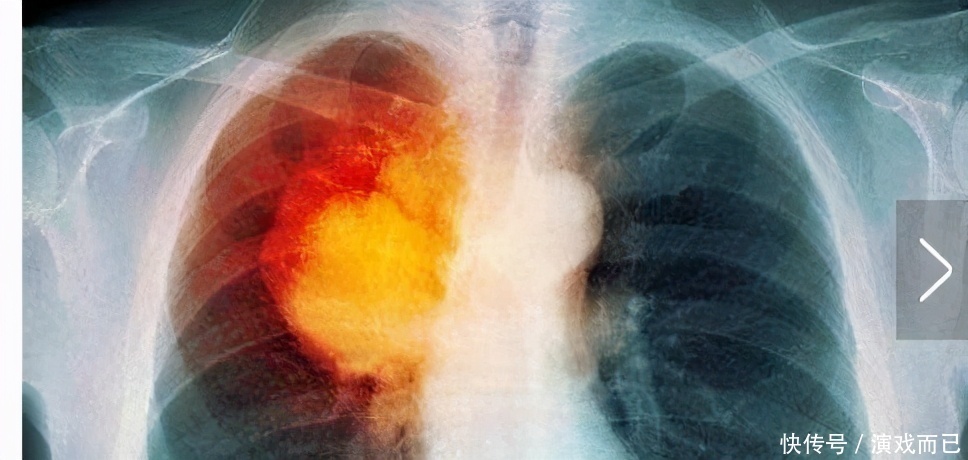

二、肺癌得以控制

丁先生耳下生一个肿瘤,被诊断是末期癌细胞,用放射疗法之后,癌细胞转移 到肺部,成为肺癌,被宣告已经是到了无法治疗的阶段。丁先生以积极的态度,回 到家里实行鲜汁疗法。目前已经控制住癌细胞的蔓延,体力渐渐恢复,而且几乎可 以回到工作岗位。